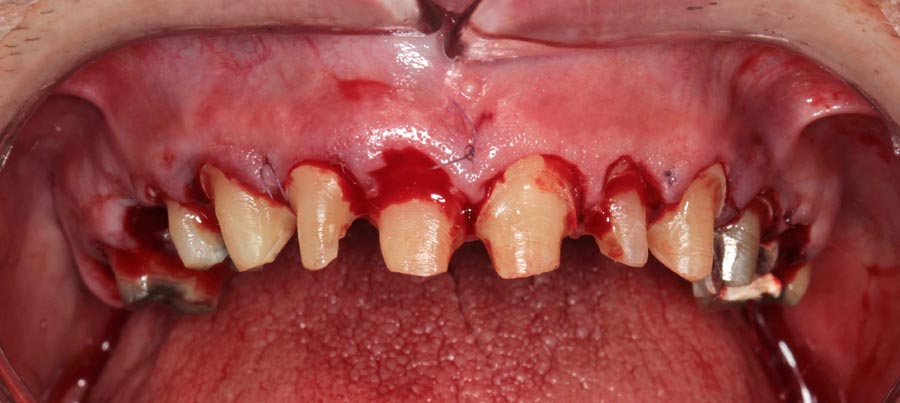

Patient wanted to see what longer, prettier teeth would look like. Crown preparations to prepare for crown lengthening and temporary crowns/bridge.

This is known as hard (bone) and soft tissue (gums) crown lengthening. To have loner teeth, many patients need their bone recontoured so that the gums do not grow back down to their original position.